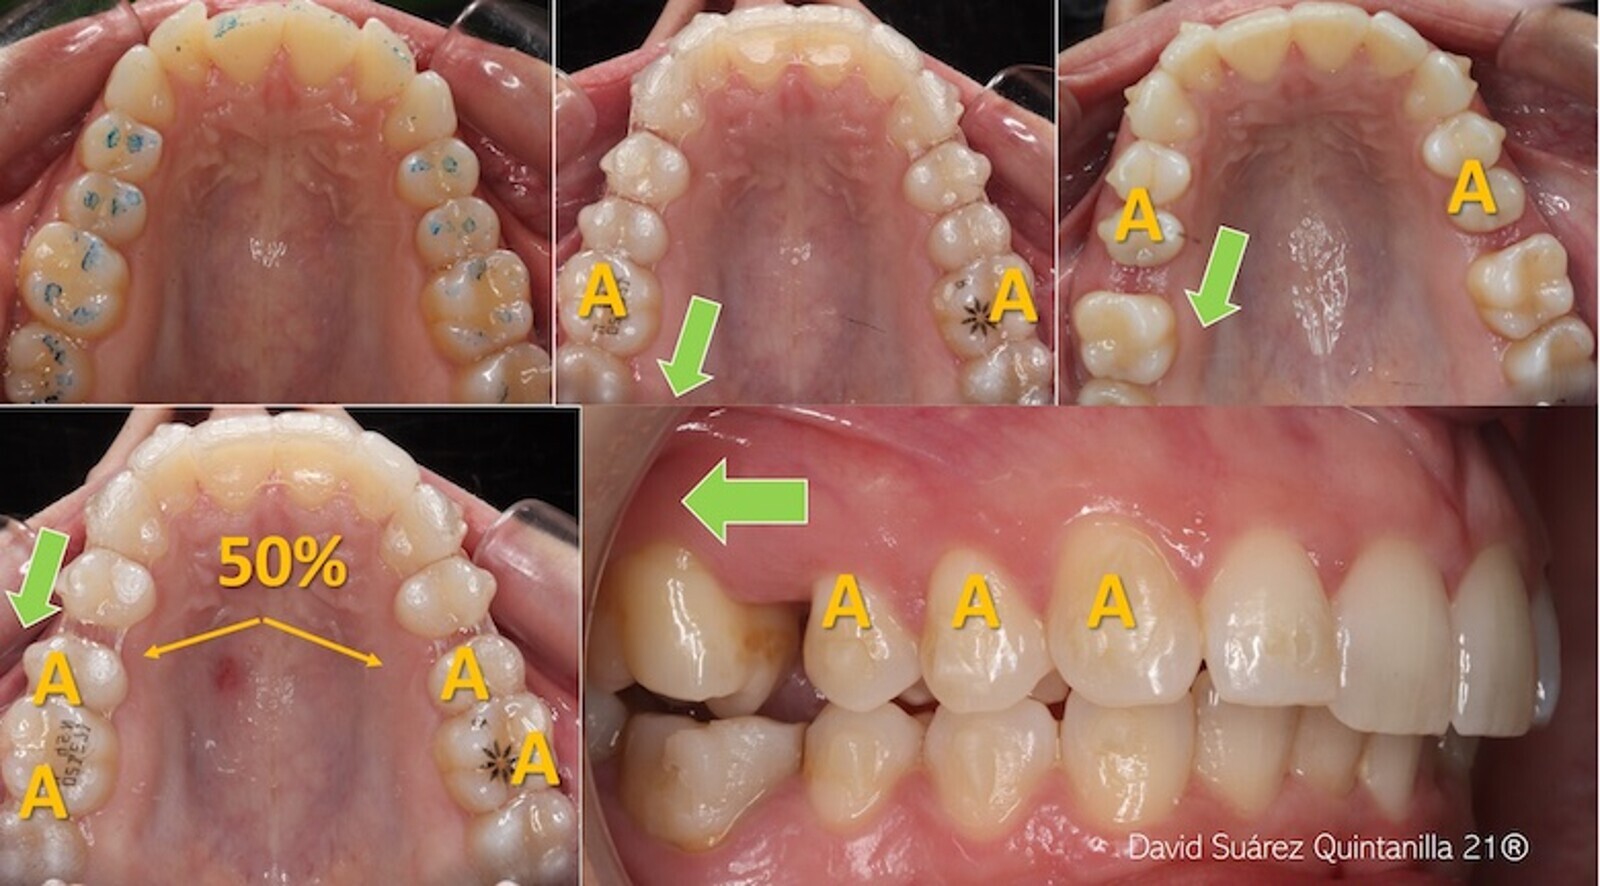

Diferentes ataches en un tratamiento de Clase II y distalamiento secuencial (figura 60) donde es muy importante ir modificando los dientes y unidades de anclaje (“A” en la figura 61) y recordar la regla del 50% (figuras 61 y 62).

Figura 60. Diferentes ataches en un tratamiento de Clase II y distalamiento secuencial.

Figura 61. Es muy importante modificar los dientes y unidades de anclaje (“A”).

Figura 62. Se debe recordar la regla del 50%.